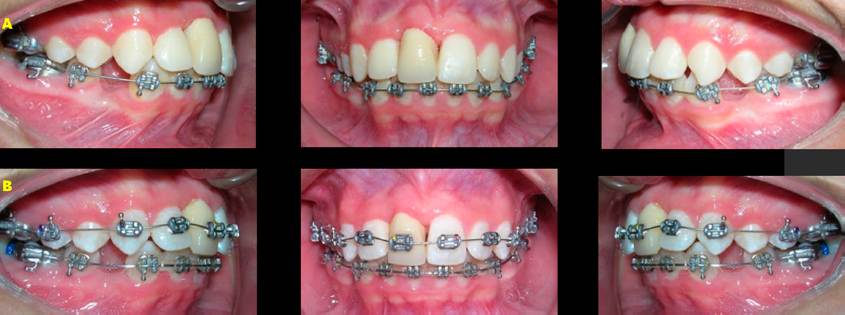

Figura 4 Fotografías de avance. A. Extraorales. B. Intraorales con aparatología inferior. C. Serie de radiografías dentoalveolares, donde se observa el diente trasplantado sin reacción apical.

El tratamiento de conducto se realizó en la semana cuatro para reducir el riesgo de desarrollar complicaciones relacionadas con el desprendimiento del tejido pulpar, sus nervios y apoyo vascular24. En cuanto al refinamiento oclusal, este se realizó mediante la colocación de aparatología fija, extracciones de primeros premolares superiores, alineación, nivelación, cierre de espacios y culminación de la etapa de ortodoncia, para cumplir con los principios de una oclusión estable y respetar las demandas estéticas del paciente. Durante la colocación de los dispositivos, cuidamos la posición de los brackets, ya que es de suma importancia brindar paralelismo de raíz. La nivelación y alineación forman parte de un proceso complejo en el que todas las coronas, incluyendo el diente 11 con provisional (Figura 5) se mueven al mismo tiempo y en diferentes direcciones desarrollando fuerzas recíprocas entre ellas, lo que puede ser de gran ayuda para orientar los movimientos a nuestro favor y así poder lograr las características de una oclusión natural y mejorar las características de los tejidos blandos del perfil facial.

Figura 5 Progreso del tratamiento. A. Ajuste y colocación de provisional en el diente 11. B. Colocación de aparatología superior.

Al finalizar el tratamiento de ortodoncia se retiraron los aparatos fijos y se colocaron retenedores. En ortopantomografías y laterales de cráneo, se puede identificar la salud periodontal y endodóntica del diente trasplantado, así como la integridad radicular.

En este caso no se encontraron cambios oclusales y el índice de irregularidad fue de 2 mm en la arcada inferior, según se evaluó después de 12 años de finalizado el tratamiento. Se lograron relaciones de clase I en molares y caninos en ambos lados, la sobre mordida horizontal y vertical fueron ideales. El seguimiento a largo plazo (12 años) del diente trasplantado en el sitio del diente 11, se ha mantenido estable y funcional (Figura 6). La raíz del diente trasplantado se encontraba con hueso cortical deficiente al inicio del tratamiento, por lo que durante todo el tratamiento se utilizaron fuerzas ligeras para evitar la reabsorción de la raíz y obtener la máxima estabilidad (Figura 7).

Los valores cefalométricos de pretratamiento, postratamiento y evaluación cefalométrica 12 años después del tratamiento de ortodoncia están en la Tabla 1. Las superposiciones entre los tres trazados cefalométricos muestran cambios en las medidas cefalométricas al comienzo de T1, T2 y T3. El análisis cefalométrico postratamiento destaca efectos dentarios, con retro inclinaciones de la arcada superior e incisivos inferiores, modificando también un aumento del ángulo interincisal. En la evaluación a los 12 años del tratamiento no se observan cambios en la posición de los incisivos superiores e inferiores (Figura 8).